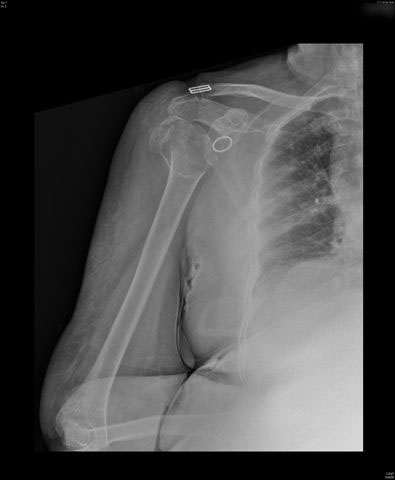

Fractura impactada de húmero .

Fractura de húmero, intensa desviación de fragmentos

Fractura de húmero.

Fractura compleja de húmero.